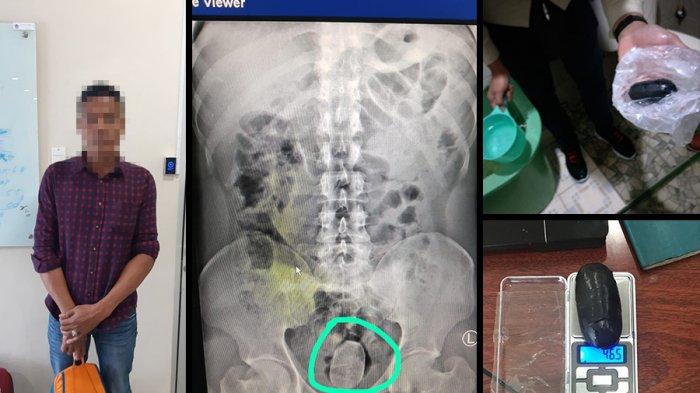

Kepala Bidang Penindakan dan Penyidikan Bea Cukai Sumatera Utara, Sodikin, menungkapkan modus yang digunakan pelaku untuk bisa menghindar dari kecurigaan petugas. “Modusnya dengan ‘back door’ atau adalah dengan memasukan barang ke dalam anus untuk bisa lolos dari pengawasan petugas,” ungkap Sodikin.

Ia menambahkan bahwa pelaku berinisial AM telah diatensi petugas sejak kedatangannya di Indonesia. Petugas lantas melakukan pemeriksaan badan, ion scan, dan rontgen. Dari pemeriksaan tersebut terlihat ada benda asing di dalam tubuh pelaku.

“Petugas kemudian meminta pelaku untuk mengeluarkan benda tersebut dari dalam tubuhnya. Benda tersebut berupa kapsul hitam seukuran kepalan tangan anak-anak. Kemudian petugas melakukan uji narcotest hasilnya positif narkotika jenis sabu seberat 46,5 gram,” ungkap Sodikin. Petugas langsung menyerahkan pelaku kepada Ditres Narkoba Polda Sumatera Utara untuk pemeriksaan lebih lanjut.